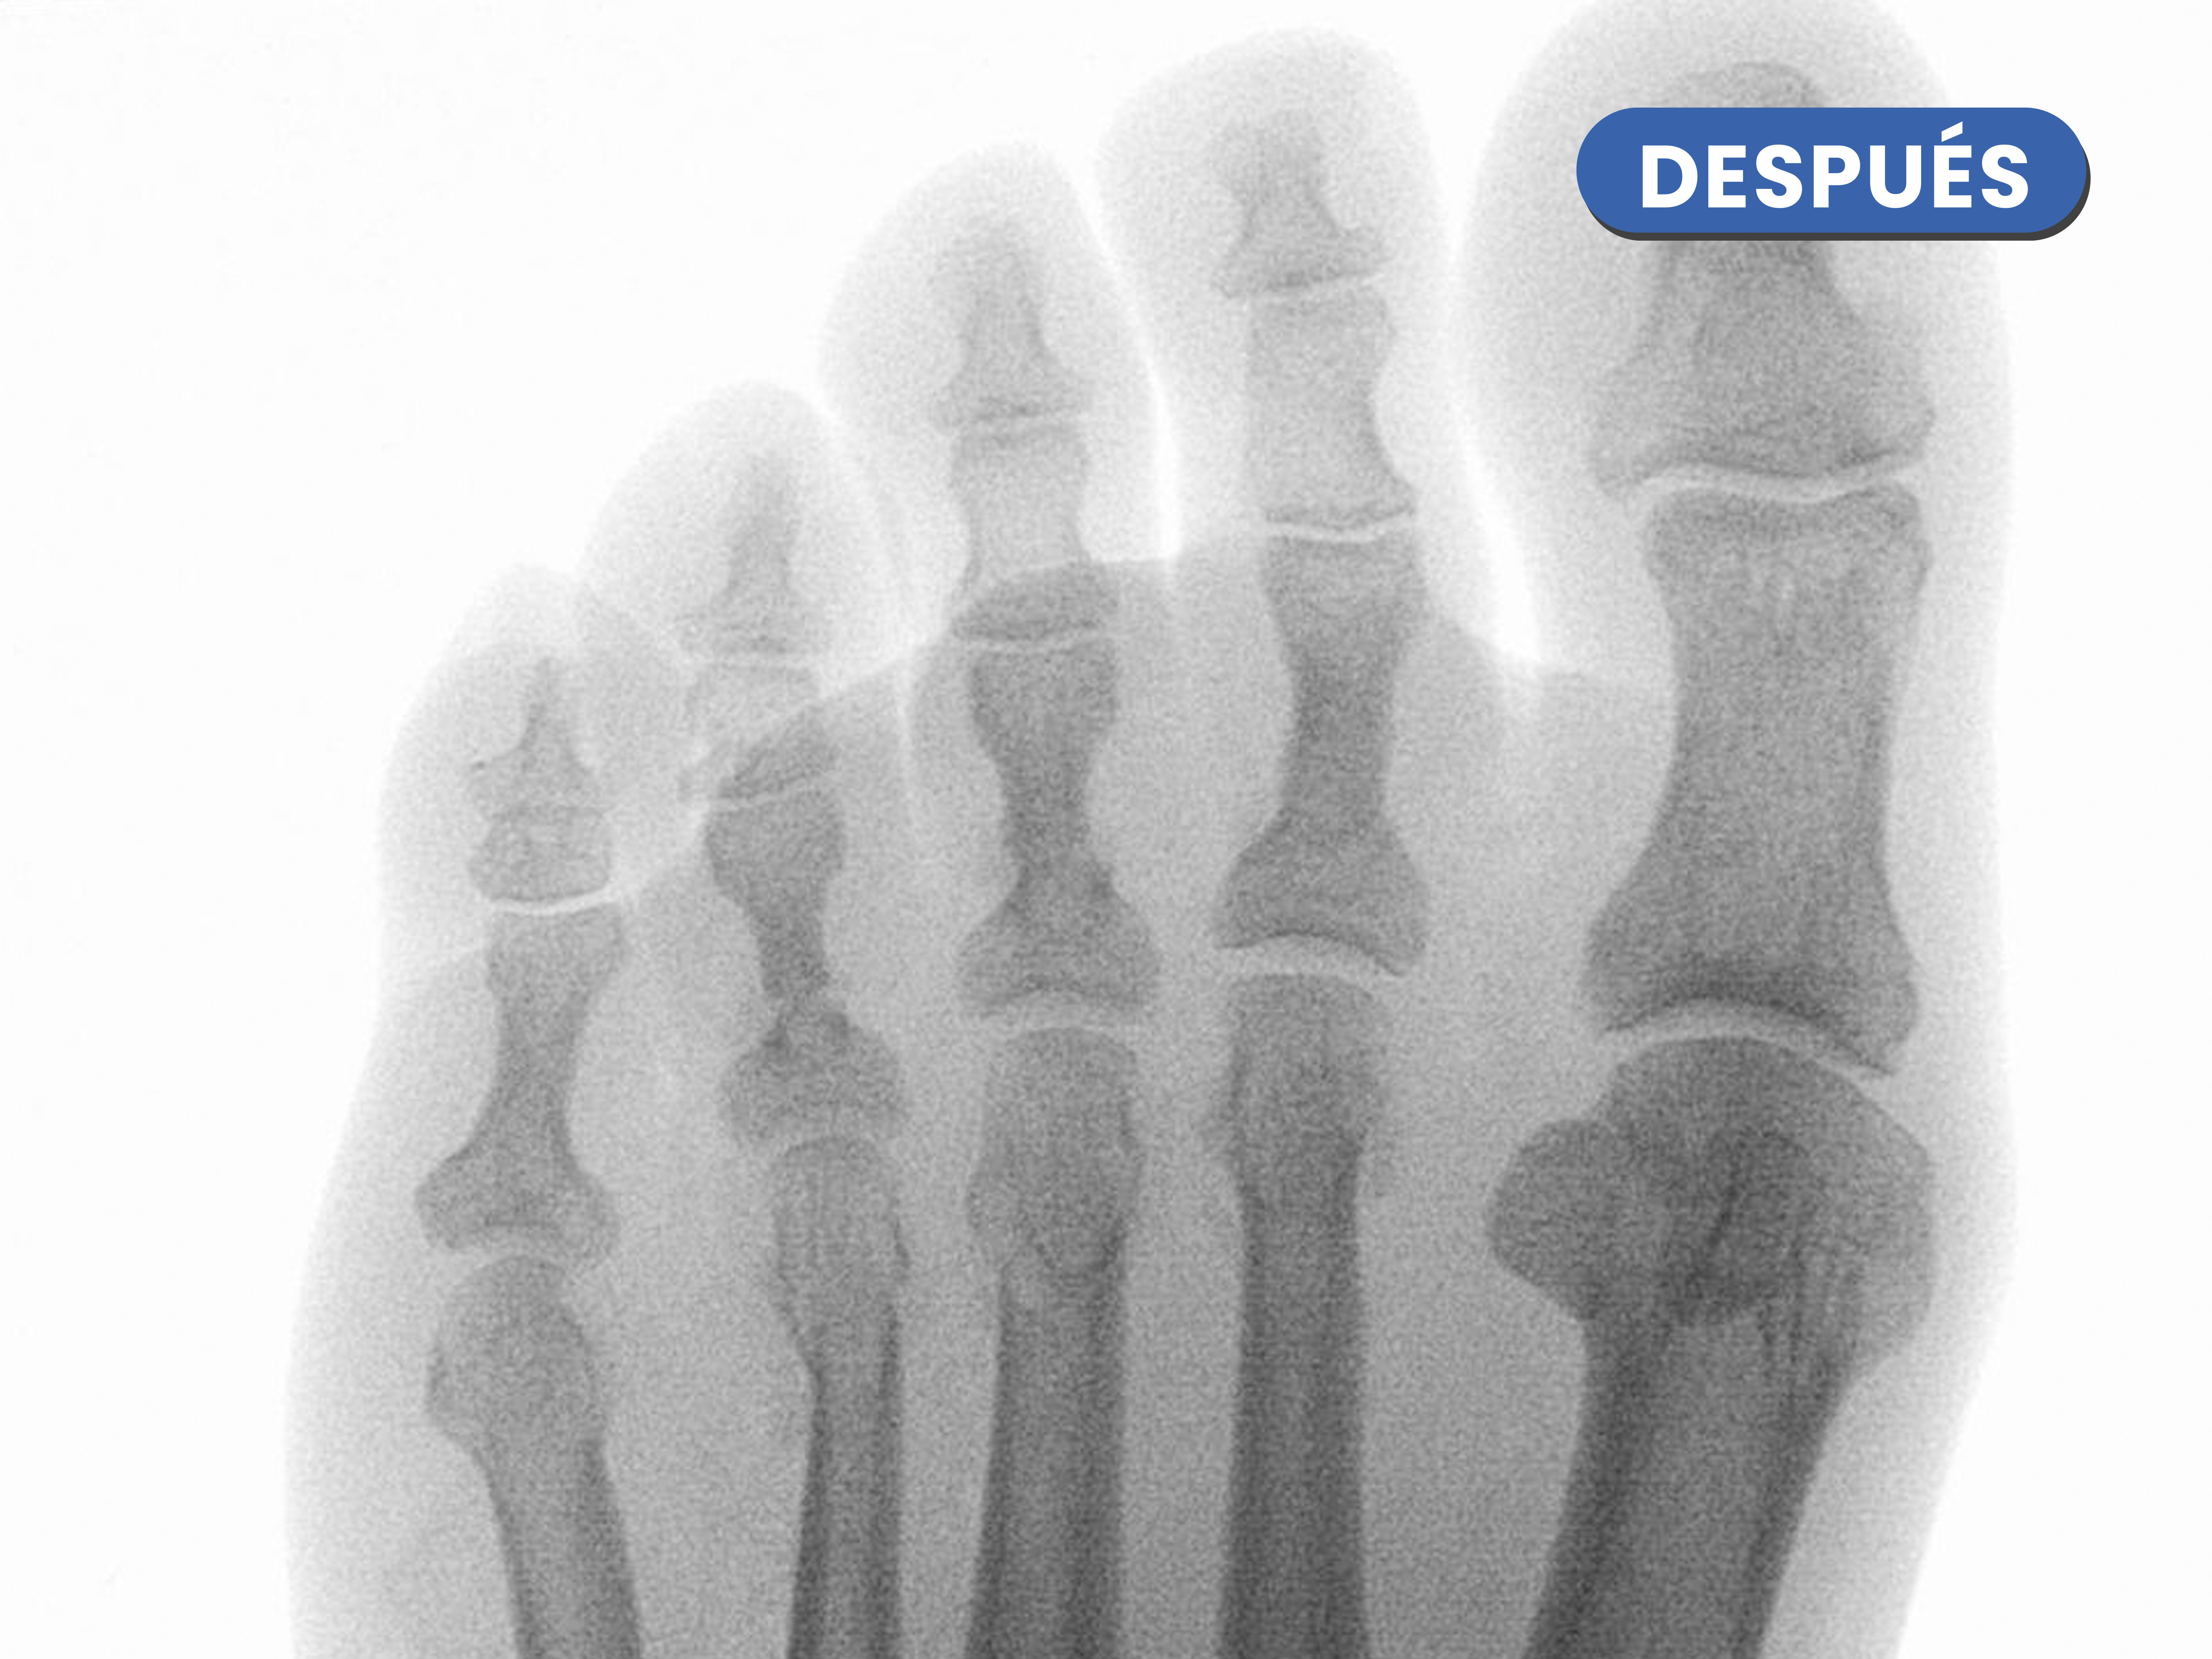

Casos reales resueltos con Cirugía de Mínima Incisión (CMI)

Te mostramos casos reales resueltos mediante cirugía de mínima incisión por el Dr. Rubén Lorca y su equipo.

Mueve las flechas para visualizar el antes y después.

En este caso realizamos una osteotomía acortadora del tercer metatarsiano al ser más largo estaba creando una sobrecarga en la zona, se puede visualizar como disminuye de tamaño en la imagen de después de la cirugía.